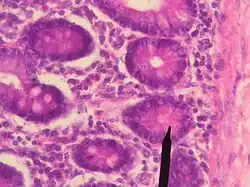

Энтероциты бокаловидные или бокаловидные клетки (лат. enterocytus caliciformis) — продуцирующие слизь клетки эпителия слизистой оболочки кишечника позвоночных животных и человека. В бокаловидных клетках накапливаются гранулы муциногена, которые, абсорбируя воду, набухают и превращаются в муцин (основной компонент слизи). При этом клетки обретают форму бокала, суженного у основания (где находится ядро) и округлой широкой в апикальной, верхней части. Затем набухшая верхняя часть бокаловидной клетки разрушается, слизь переходит в просвет органа, клетка приобретает призматическую форму и снова начинает накапливать муциноген. Кроме кишечника, бокаловидные клетки имеются в слизистой оболочке дыхательных путей, в конъюнктиве глаз, протоках поджелудочной и околоушной желёз.[5]

Энтероциты ацидофильные (синонимы: клетки Панета, энтероциты с ацидофильными гранулами; лат. enterocytus cum graulis acidophilicis) — трапециевидные клетки эпителия кишечных крипт, в апикальной части которых находятся ацидофильные гранулы, содержащие пищеварительные ферменты кишечного сока. Составляют примерно 1 % от общего количества энтероцитов тонкой кишки.[2]